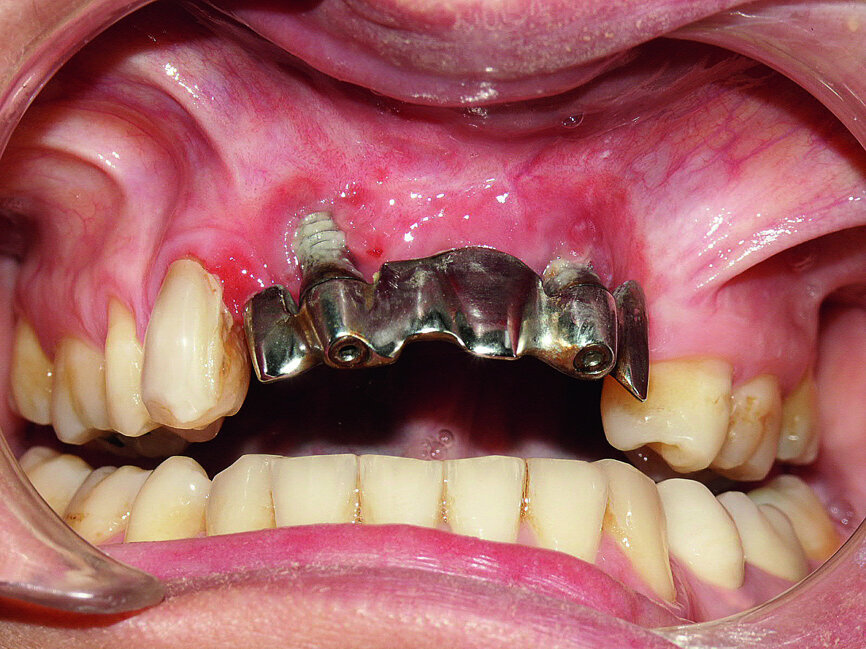

In the following step, the prosthesis was attached in the mouth with screws and the necessary occlusal verification was conducted, including maximum intercuspation, protrusion and lateral excursion. The natural canine on the right was also equipped with a verification tooth. It should be noted, that in lateral excursion on the left, with the antagonist being the original tooth equipped with its periodontal ligament receptors, the canine function was retained; however the group function, which is usually preferred, was neurophysiologically inept (Figs. 28 & 29).

The patient’s smile showed that the incisors were now well balanced and in line with the face’s sagittal plane. Lip support appeared to be correct and, as often is the case, this would all be validated by the patient’s surrounding friends and family (Fig. 30).